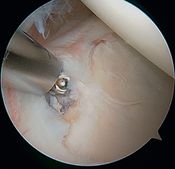

In 1985, Andrews et al. were the first to see, under arthroscopy, superior labral tears (Figure and Video) in 36 throwing athletes (sometimes associated with articular rotator cuff tears).[5]

Articular rotator cuff tears

They reported that simple debridement allowed 85% of athletes to resume their sport at the same level (Figure and Video).

Simple labral debridement